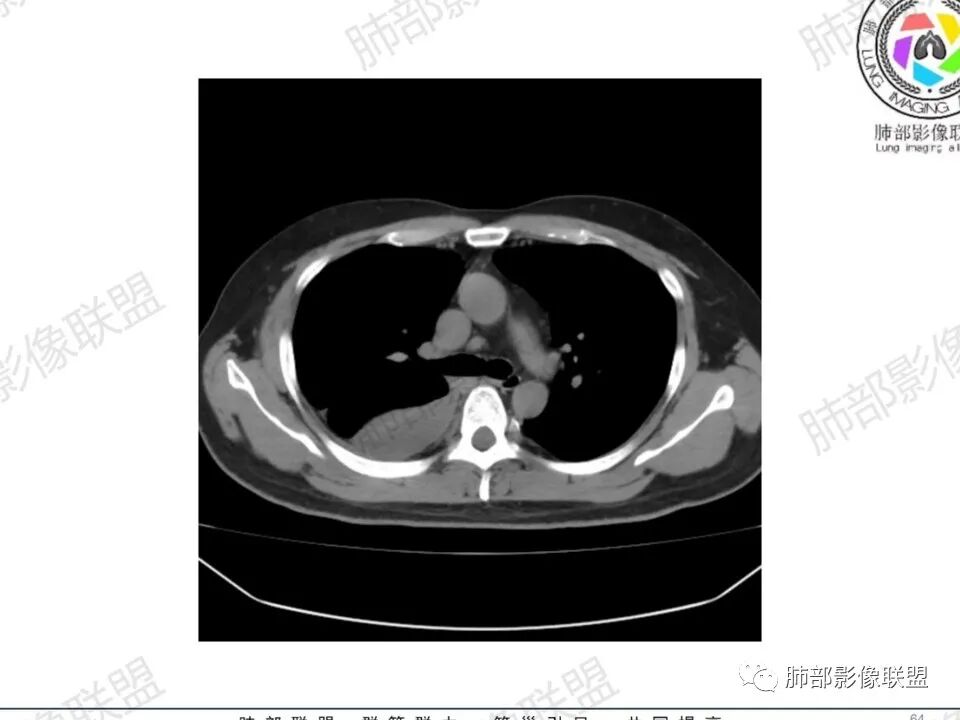

双肺多发结节,胸膜下为主,部分可见空洞。左肺上叶尖后段结节较大,分叶毛刺,周围可见长条索及小斑片影,内空洞比较光滑,内侧壁可见支气管通过。右肺下叶后基底段不张实变,后侧积液,右侧水平裂积液,右侧膈胸膜纵膈胸膜增厚积液,右侧侧胸膜肥厚,考虑1:一元金葡。2二元:金葡,左肺上叶结核。

感觉还是金葡入血形成SPE可能性较大,胸水+楔形影+胸膜结节

中年男性,左手中指及胸壁疼痛伴发热来诊,影像见双肺多发结节,胸膜下分布为主,部分结节可见空洞,边缘模糊。左肺上叶尖后段结节较大。右肺下叶后基底段不张实变,右侧叶间裂及右侧胸腔积液,右侧侧胸膜肥厚。考虑金葡菌感染,血播SPE。

有胸腔积液更提示血道来源

空洞内壁光滑,偏心厚壁空洞,张力高

胸水,部分包裹

支持血道来源感染性病变,金葡菌肺炎首选